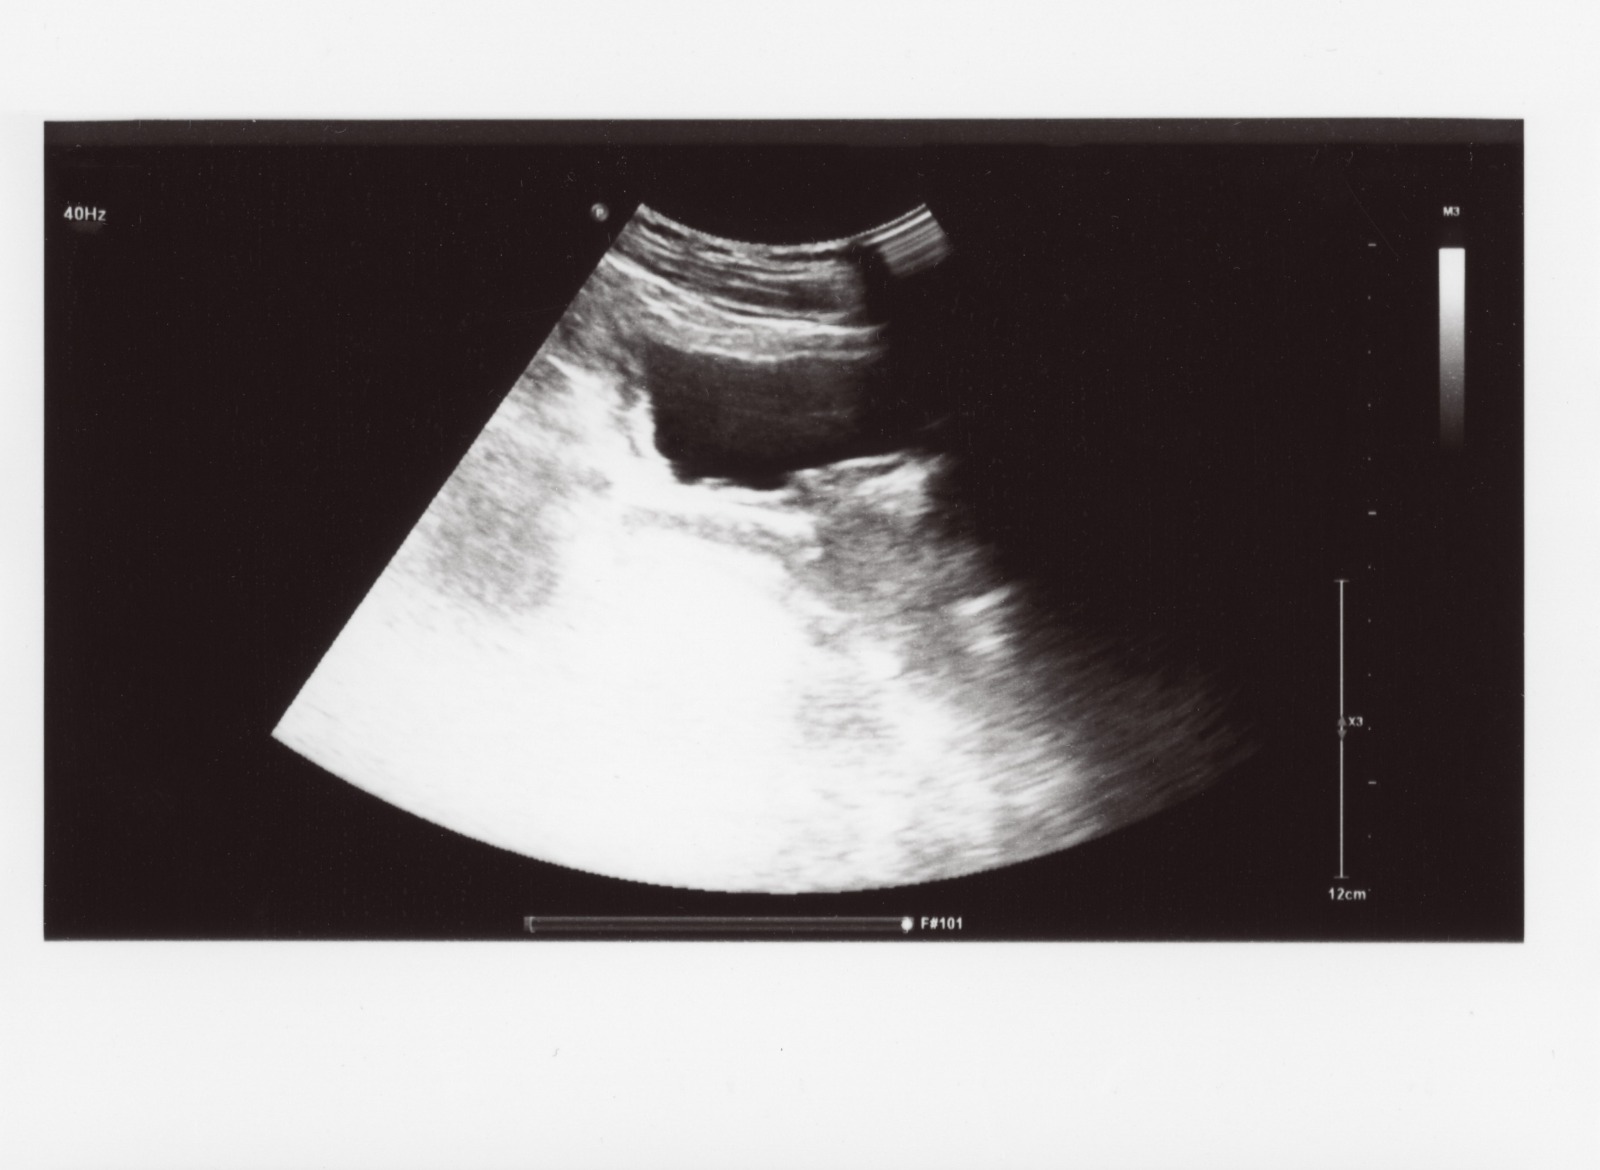

Kepastian blighted ovum hanya dapat diketahui melalui USG.

Blighted ovum sering kali dapat ditemukan melalui USG transvaginal. Akan tetapi, tidak selalu kondisi ini diketahui sejak pemeriksaan pertama.

Umumnya, pertama kali seorang wanita memeriksakan diri ke dokter spesialis obgyn adalah saat usia kehamilannya berada di sekitar 5-6 minggu, atau telat terlambat menstruasi sekitar 1-2 minggu.

Pada masa ini, kantung kehamilan sudah terbentuk, tapi detak jantung janin terkadang belum terdengar. Dengan demikian, untuk memastikan kehamilan berkembang dengan baik atau tidak, dokter akan meminta Anda untuk datang pada 3-4 minggu mendatang.

Pada pemeriksaan selanjutnya, saat perkiraan usia kehamilan telah mencapai 9-10 minggu, detak jantung janin jika berkembang seharusnya lebih kuat. Itu sebabnya, pada tahap ini dokter bisa mengetahui apakah kehamilan berkembang sesuai yang diharapkan atau tidak.

Pada kehamilan kosong, dokter tidak dapat mendengar detak jantung janin, yang menandakan kantung kehamilan kosong.